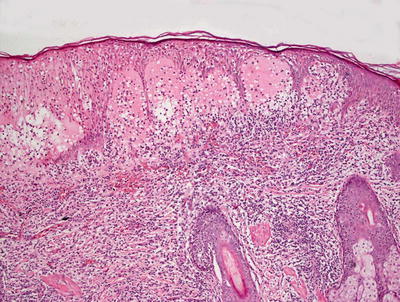

3.8.2 Histology

The histologic findings in hydroa vacciniforme are not specific. The epidermis is markedly spongiotic in early lesions, progressing to reticular degeneration and ultimately necrosis in later stage lesions (Fig. 3.17). Within the dermis, there is a brisk infiltrate that consists predominantly of lymphocytes and histiocytes (Figs. 3.18 and 3.19). Eosinophils are not abundant. Neutrophils may be observed in ulcerated lesions, but this is likely a secondary phenomenon.

Fig. 3.18

A brisk inflammatory infiltrate in the dermis extends into the overlying epidermis in hydroa vacciniforme. Blister formation is due to spongiosis and can be at any level

Fig. 3.19

Hydroa vacciniforme is characterized by a brisk superficial and often deep dermal inflammatory infiltrate